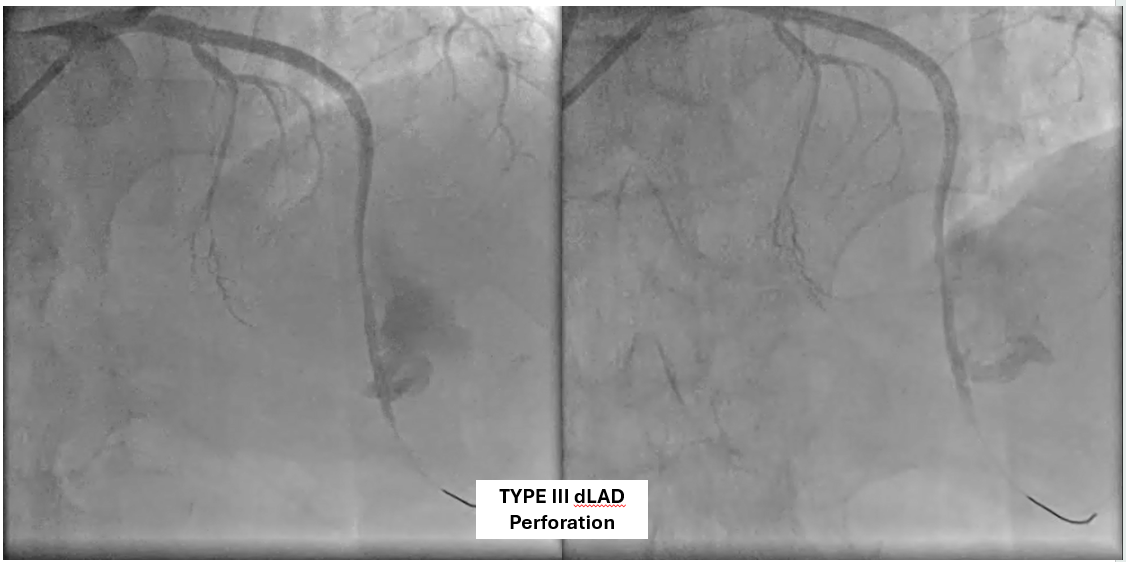

The patient underwent coronary angiography, where the team attempted to reopen the previously stented proximal mid LAD that had become occluded. After multiple revascularization efforts from ballooning to placing a ne DES in the mid LAD. A type III perforation occurred in the distal LAD during balloon inflation. Despite immediate measures including balloon tamponade and covered stent deployment, the perforation remained visible on follow-up angiography.

A covered stent was deployed in the distal LAD in an attempt to seal the coronary perforation; however, angiography showed that the Type III perforation persisted despite the intervention. Additional balloon inflation within the stent was performed, but the leakage could not be completely sealed. The patient remained hemodynamically stable without signs of cardiac tamponade or pericardial effusion. The following day, repeat coronary angiography was conducted to reassess the condition, which confirmed persistent contrast extravasation from the LAD into the left ventricular cavity, indicating the formation of a coronary–ventricular fistula. Given the hemodynamic significance and the risk of progressive left ventricular dysfunction due to continuous shunting, a multidisciplinary decision was made to proceed with surgical correction. The patient subsequently underwent successful LAD–LV fistula patch repair combined with. Surgical repair remains the definitive management for such cases, and early recognition with timely intervention is crucial to restore cardiac function and prevent irreversible myocardial damage.